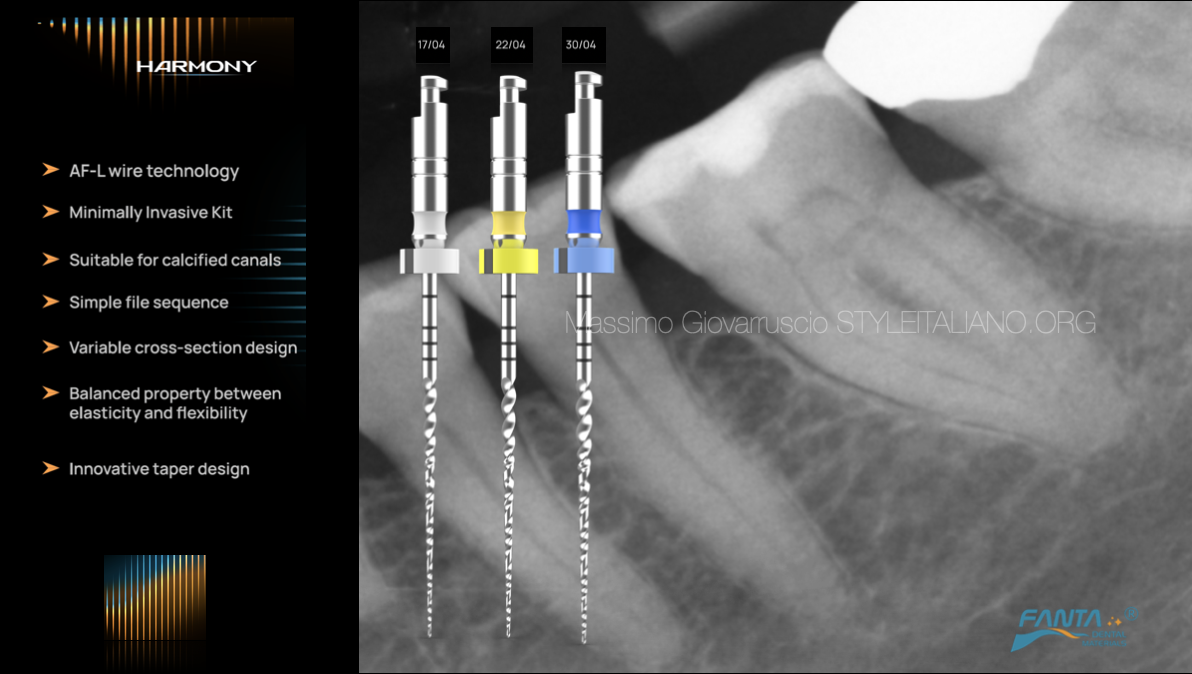

The variable cross section and the innovative taper design of Harmony files make them indicated for treating curved and calcified canals. A balanced property between elasticity and flexibility give to the files the great chance to treat the curved canal with no transportation and respecting the anatomy in all minimally aspects.

Fig. 1